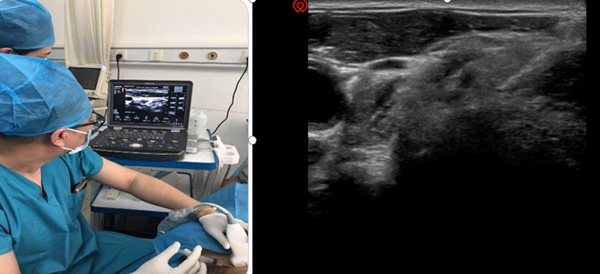

科室以超声可视化技术为核心,打造精准镇痛体系,彻底告别传统镇痛“盲探”模式。超声可清晰呈现深层解剖结构,全程实时引导穿刺操作,确保神经阻滞、针刀松解等治疗的精准度与安全性,让每一次治疗都直达病灶、有的放矢。超声引导下神经阻滞术、超声引导针刀松解术等特色技术,适配多种疼痛病症,创口微小、恢复快速、疗效确切,吸引河北、内蒙古等多地患者慕名就诊,用精准疗效赢得广泛认可。

超声可视化注射治疗技术

超声可视化神经阻滞治疗技术

超声可视化针刀技术技术